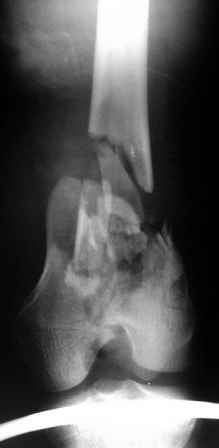

Рентгенограммы.

На рентгенограммах перелом не "н/3" бедра, что подразумевает диафиз, а перелом дистального суставного конца - крупные фрагменты мыщелков, метафиз фрагментирован, т.е. по классификации OTA/AO это 33C2.

Право слово, классификация переломов существует не зря, она помогает и выбрать вариант остеосинтеза, и даже в отсутствие рентгенограмм можно более точно обозначить проблему.

Наиболее широко распространенный подход в такой ситуации - после репозиции мыщелков использовать пластину с угловой стабильностью.

Можно и ретроградное штифтование, если есть соответствующий гвоздь.

При любом варианте фиксации надо избежать соблазна залезать открыто в метадиафизарную часть повреждения.

Мы бы начали с закрытой репозициии мыщелков под экраном, манипулируя джойстиками. Если не получается - миниартротомия. Сопоставленные мыщелки прошили бы спицами (резервируя место для гвоздя). Наложили бы спицевой дистрактор. И сделали бы антеградное штифтование гвоздем с

несколькими очень дистально расположенными отверстиями.

Остеосинтез при 33-С2 подразумевает относительную стабильность. Следовательно, показано использование мостовидного остеосинтеза пластиной с угловой стабильностью или интрамедуллярный остеосинтез без рассверливания с блокированием. Поскольку перелом открытый, то предпочтительнее выглядит второй вариант. Бедренный штифт Т2 производства Stryker при ретроградном введении даёт возможность межфрагментарной компрессии за счёт использования мыщелкового винта.

По прямой проекции складывается впечатление, что метаэпифизарная часть бедра расколота вдоль и латеральный мыщелок смещен книзу. Интрамедуллярный штифт "повиснет" между мышелками и есть вероятность, что при раннем начале движений мыщелки "разойдутся". Учитывая, что рана зажила первичным натяжением, предпочел бы пластину с костной пластикой. запасной вариант - аппарат Илизарова.